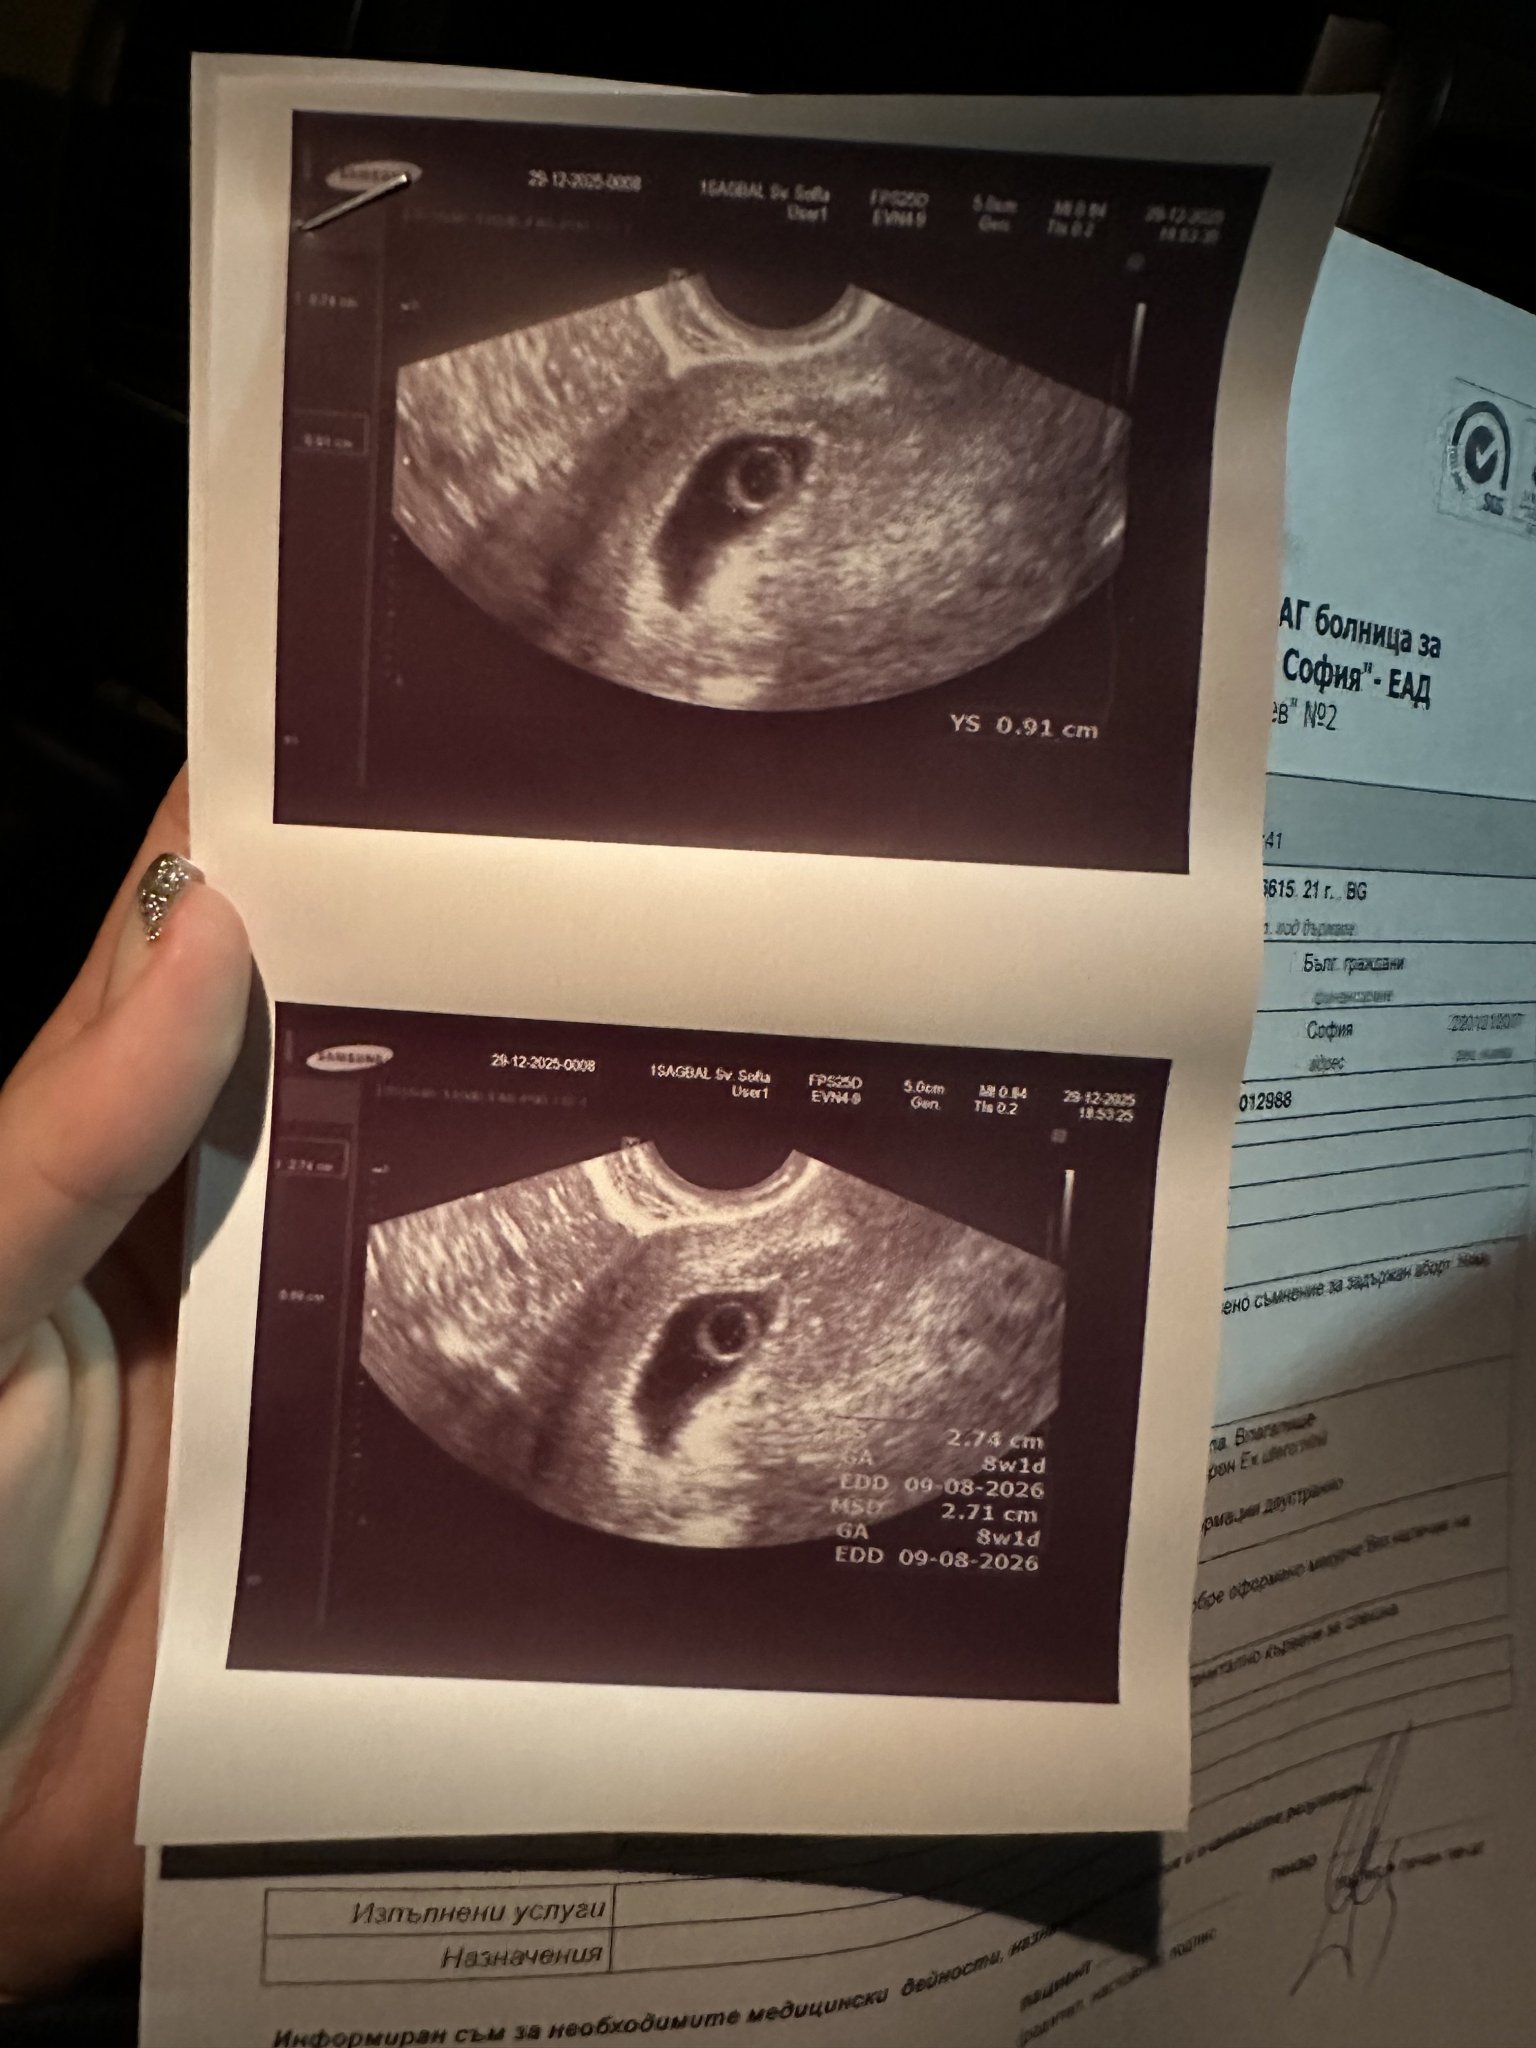

Здравейте мамита на 1-ви декември разбрах,че съм бремнна, вчера бях на втори преглед и видяха,че имам сакче, но няма ембрионче! Последния ми цикъл беше на 2 ноември, с овулацията на 16 ноември, ходих след това на второ мнение и те не видяха ембрионче! На един е преглед ме водят 6+6, а на другия 8+1 на 1-ви декември пуснах кръвни и ми излезна 208 mIU

Вчера на 29-ти пак пуснах кръвни 53390 mIU, сега и на 31-ви ще пусна отново! нямам кървене нямам болки,( но ми пуснаха направление за абсорт) Ще пробвам да прикача ехографски снимки

Благодаря, но трима доктора казват,че съм за аборт, други двама,че всичко е нормално в малка седмица съм!

От тук нататък водещо е какво се вижда на ехограф. Ако след една седмица все още няма развитие, значи бременността не се развива. Не е задължително да имате болки и кървене. При задържан аборт бременността не се развива, но тялото не изхвърля ембриона и следователно трябва да се пристъпи към МА или кюртаж.

В 7-8 седмица трябва да има вече сърдечна дейност, не е толкова "малка" седмицата. Освен ако не си с късна овулация и гестационната възраст не е реална, но при всички положения, поне точица ембрионче трябваше да се вижда в сака. Frowning1